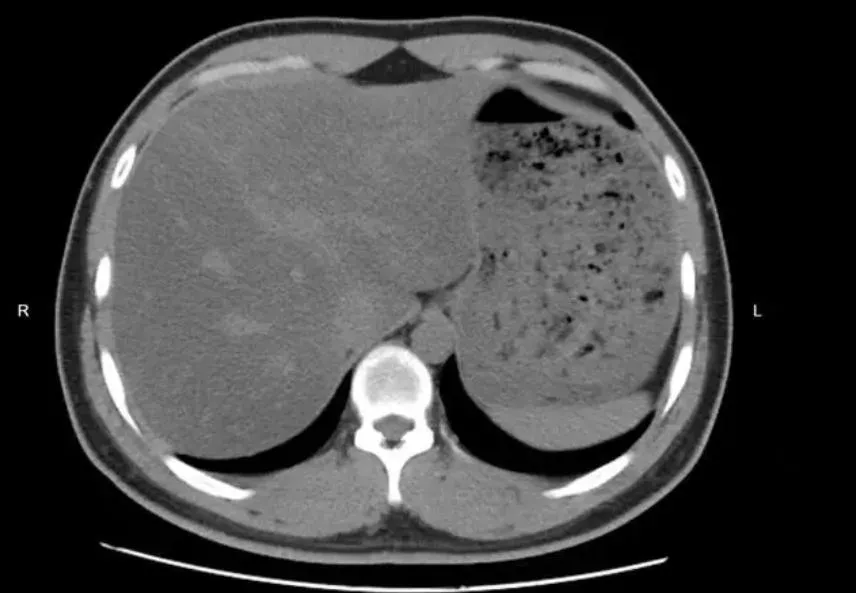

吃素吃出脂肪肝?中國浙江寧波一名29歲OL半年前體檢發現有輕度脂肪肝,於是痛下決心「餐餐水煮菜」來減肥,原本開心體重少了5公斤,不料去醫院複檢後超傻眼,脂肪肝程度反而加重為中重度!

日前劉女士來寧波大學附屬第一醫院複查,原本信心滿滿,因為這半年來,體重減掉了5公斤左右,腰腹也明顯平坦許多,不料超音波檢查出來,脂肪肝竟加重為中重度,讓她大感不解「這半年我都吃素,基本都是水煮蔬菜,怎麼會查出中重度脂肪肝呢?這不科學啊」。

複檢發現吃素半年脂肪肝竟成中重度。(圖/翻攝大象新聞)

蛋白質攝入嚴重不足反而可能加重脂肪肝

對此,寧波大學附屬第一醫院感染科楊乃彬醫生表示很多人認為,脂肪肝是胖子的專利,這個認知存在一定誤區。對由肥胖導致脂肪肝的群體來說,健康科學的減肥有利於脂肪肝的降級、逆轉,但是,不健康不科學的減肥,尤其是過度節食,蛋白質攝入嚴重不足,反而可能會加重脂肪肝。

楊乃彬指出,劉女士的「暴力減重」,半年來幾乎沒有攝入蛋白質和油脂,然而肝臟分解、代謝脂肪,都需要蛋白質,運送不出去就只能積壓在肝臟,加上長期吃水煮蔬菜,身體無法獲取所需能量,脂肪快速分解產生大量脂肪酸進入肝臟並在肝臟內長時間停留,容易引發脂肪肝。

醫師提醒,從門診來看,20%-30%的脂肪肝患者並不胖,體重正常甚至偏瘦,僅從體型和體重來判斷是否得脂肪肝並不科學,應綜合肝功能等生化檢查、肝臟B超等影像學檢查來做綜合判斷。